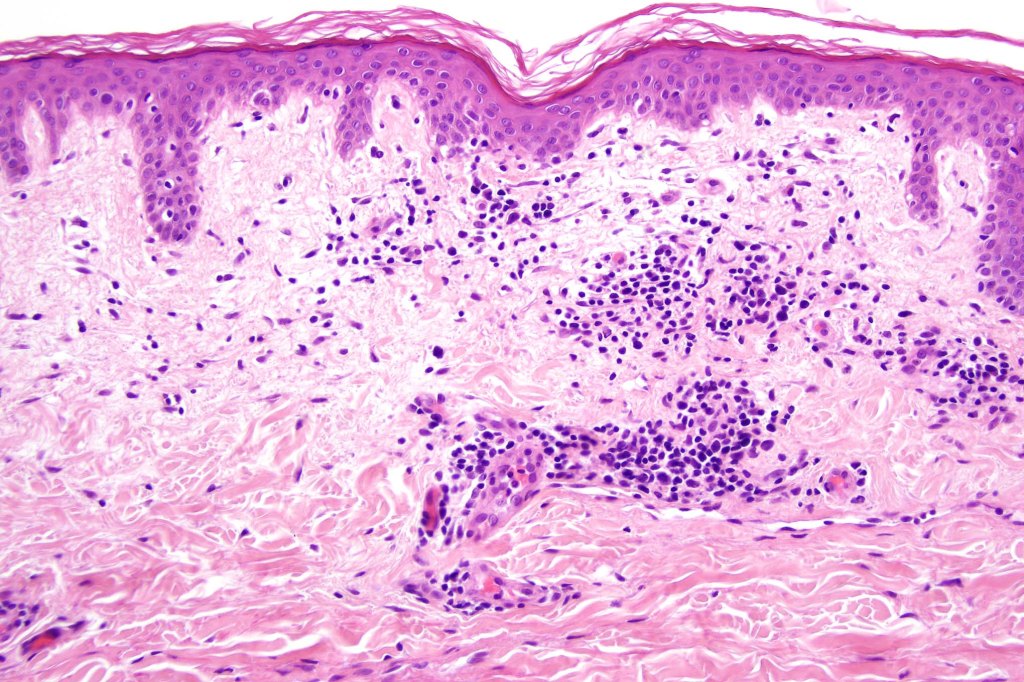

Histological features

•Variable histological features ranging from a non-specific superficial perivascular or band-like dermal infiltrate with minimal or no epidermotropism through to mycosis fungoides-like histology; can mimic atopic dermatitis